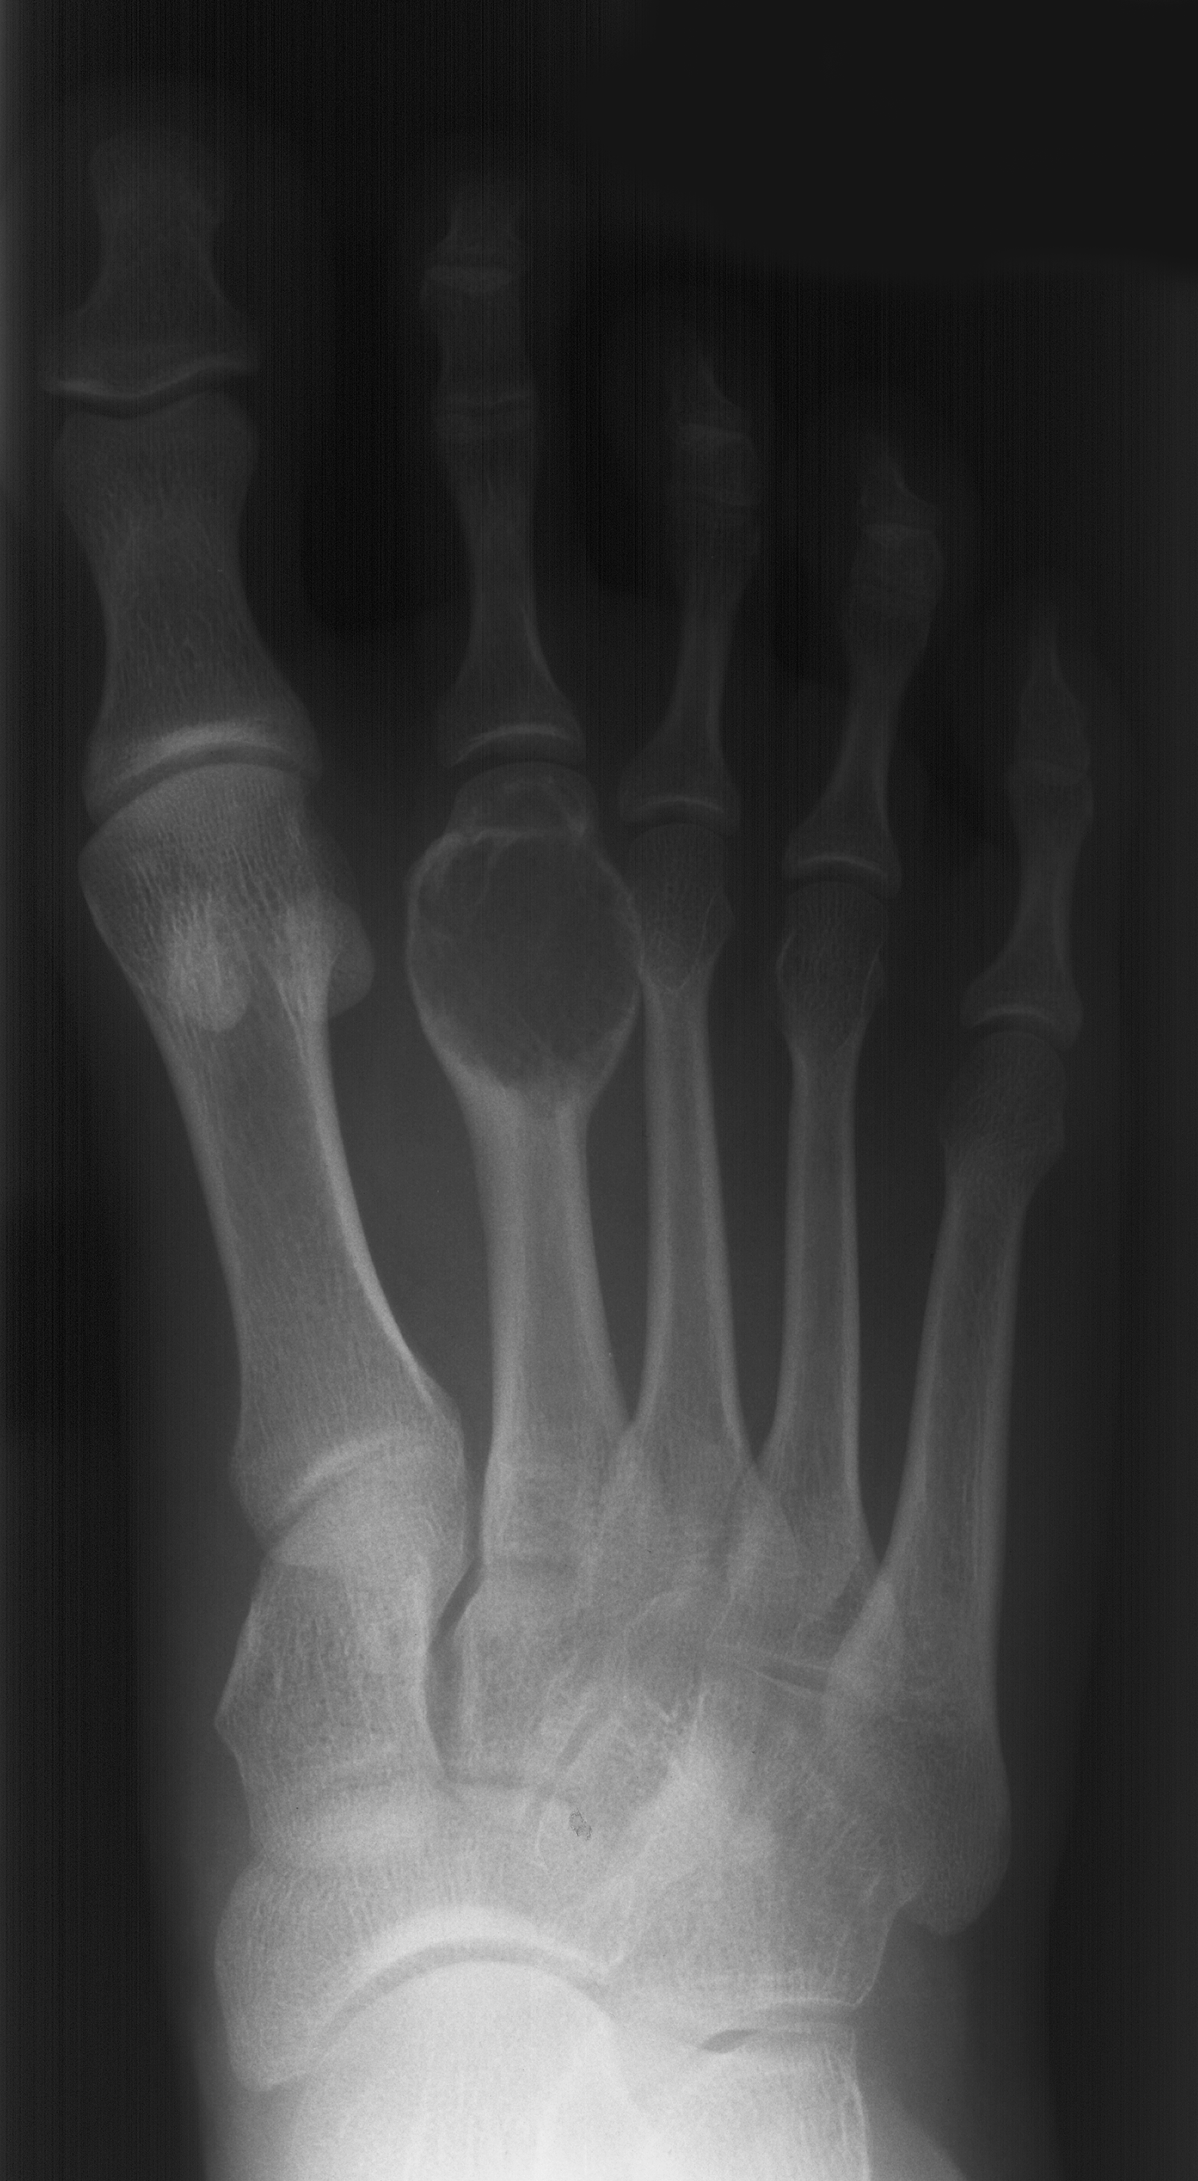

Aneurysmal bone cyst metatarsal. Benign looking expansion of the distal end of the second metatarsal. The lesion is cystic with fluid-fluid levels evident on the STIR image.

16-year-old girl complaing of pain and swelling of the foot.